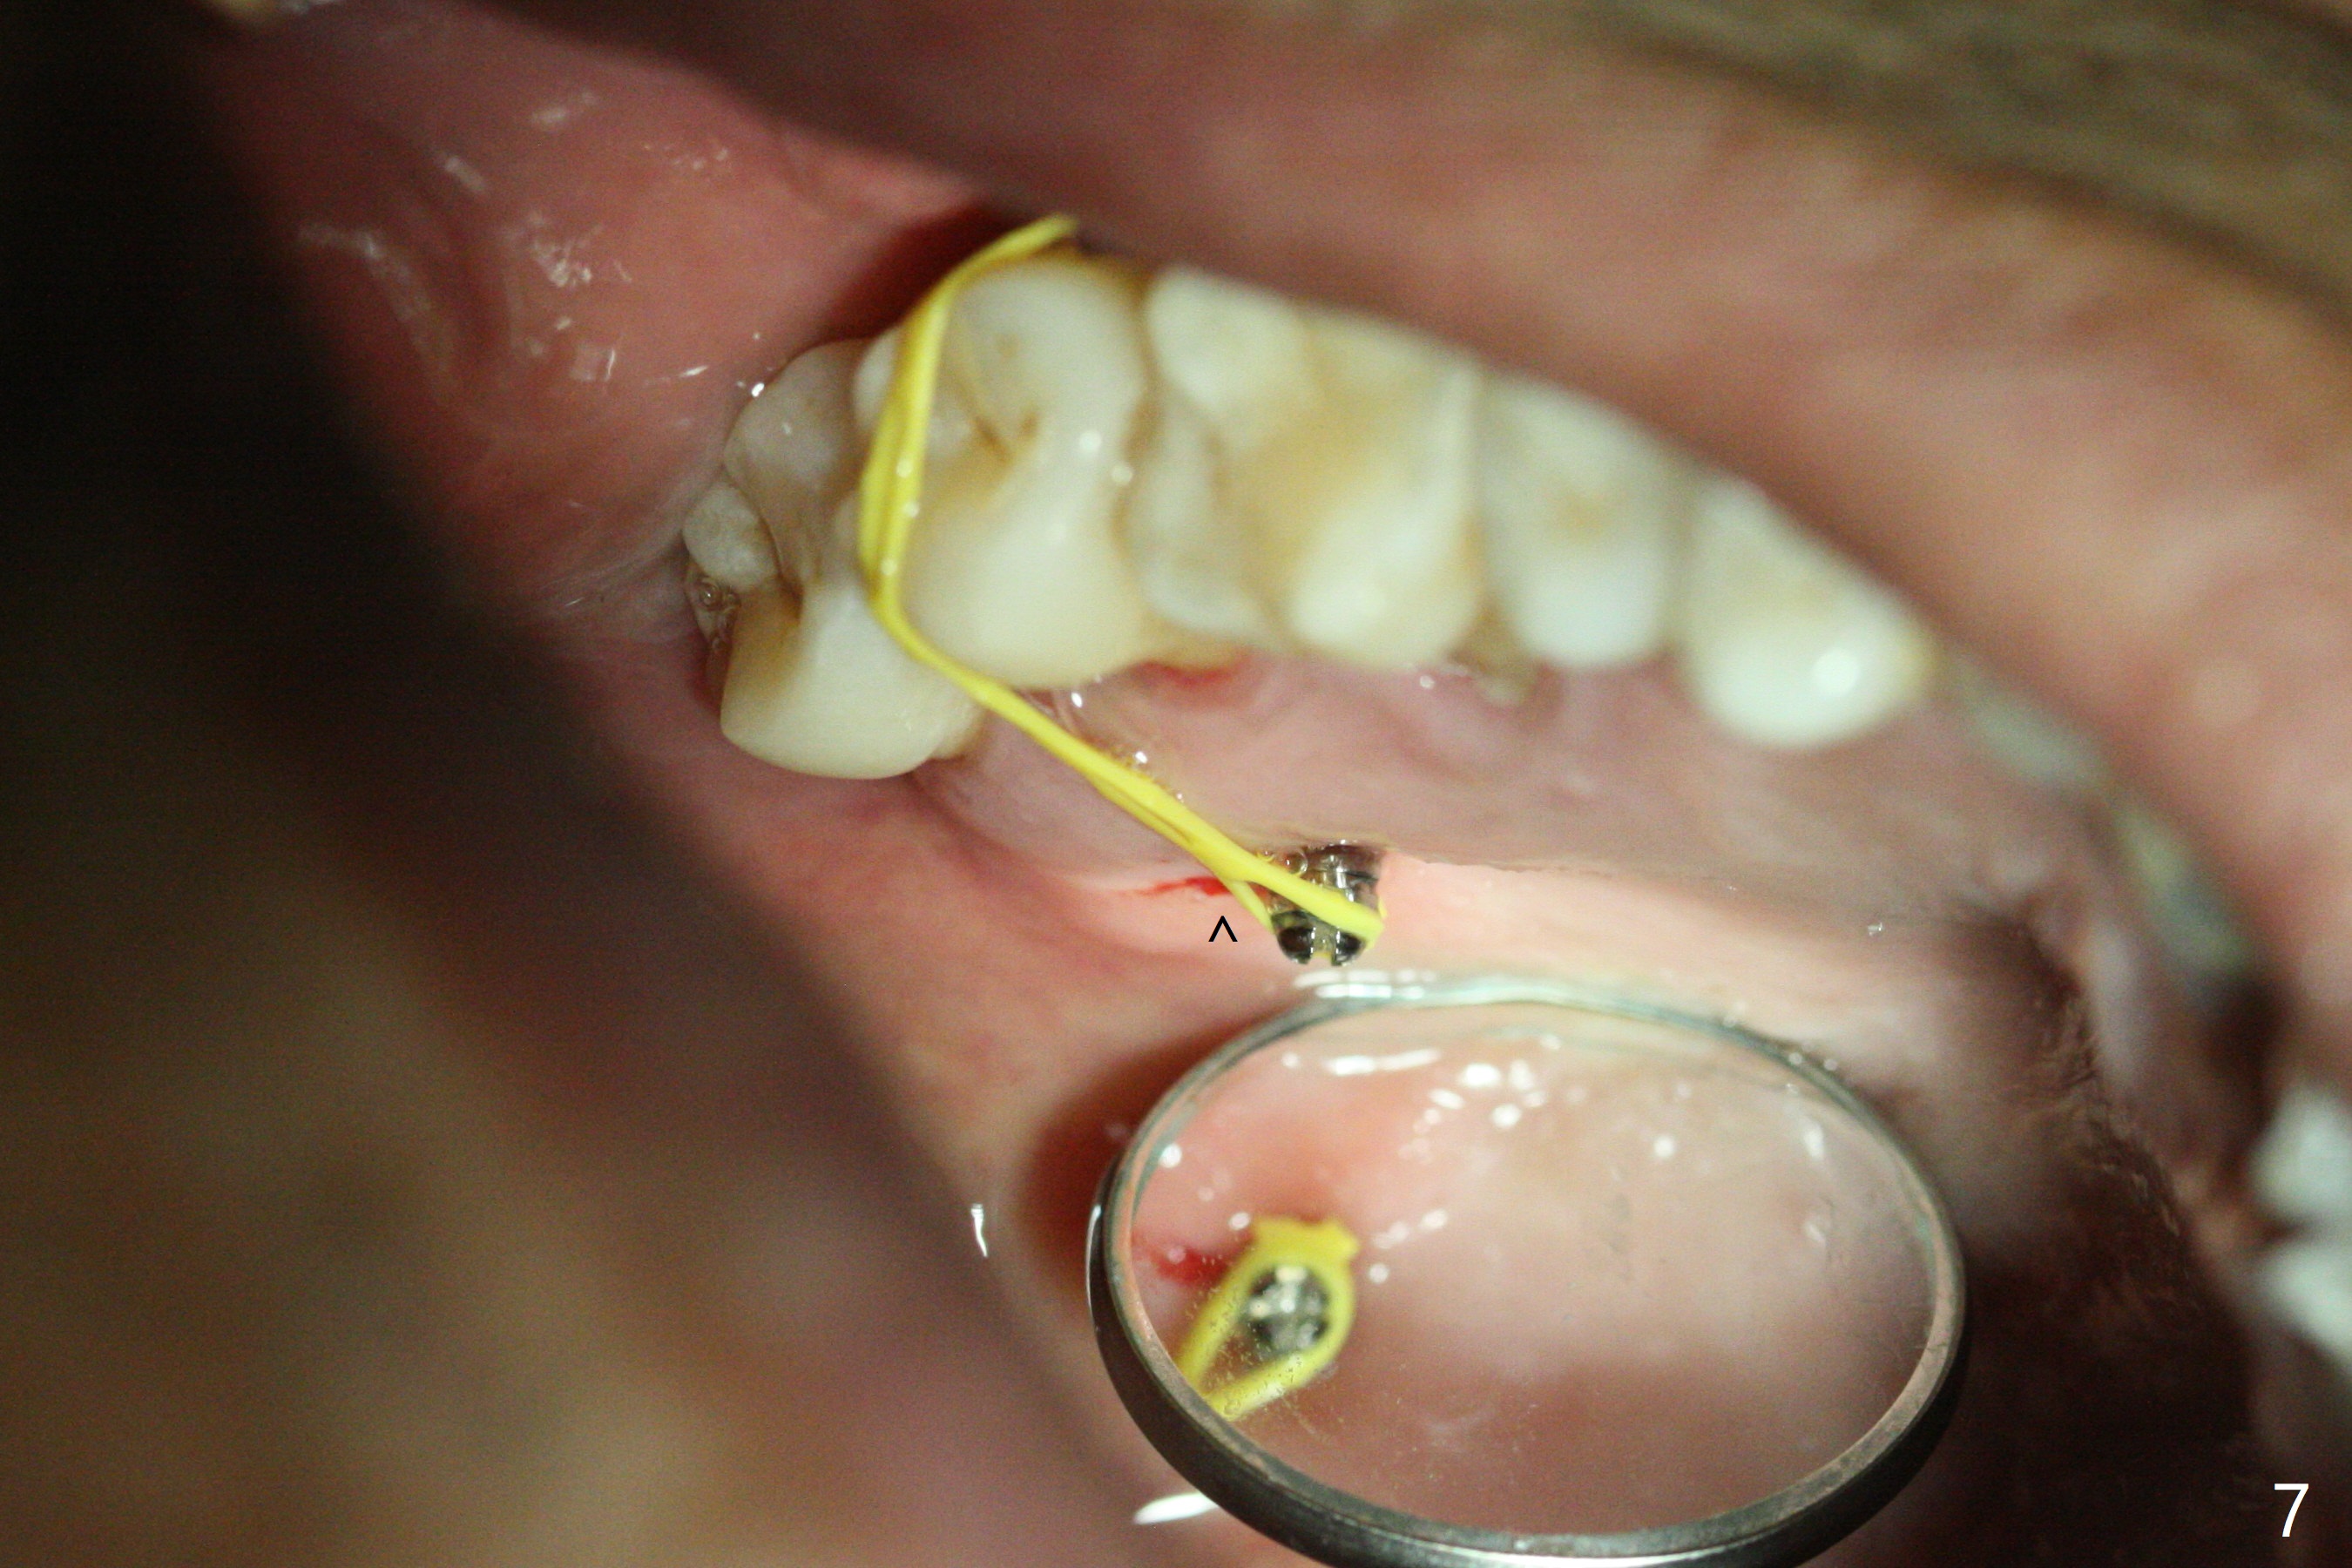

When 6 and 8 mm Tomas pins are initially placed mesiobuccal (MB) and distolingual (DL) to the supraerupted tooth #2, PA is taken (Fig.1), which shows that the DL one seems too distal. The mini implant is removed and placed more mesial (Fig.2, 7 (^: original entry)). When the patient experiences a little pain as the DL implant is being placed deeper with minimal local anesthetic, CT is taken. In fact the latter is between the apices of the teeth #1 and 2 (Fig.3 (L: lingual view of 3D image)). The implant is later placed deeper with minor angular change as well as more anesthetic. There is an advantage to place the miniimplants apically; there is more space. But the MB implant is a little bit mesial (Fig.4). After withdrawal, the trajectory of the implant is changed somewhat as indicated by a red arrow in Fig.5). Note the apical placement of the minimplants (close to mucogingival junction, Fig.6,7).